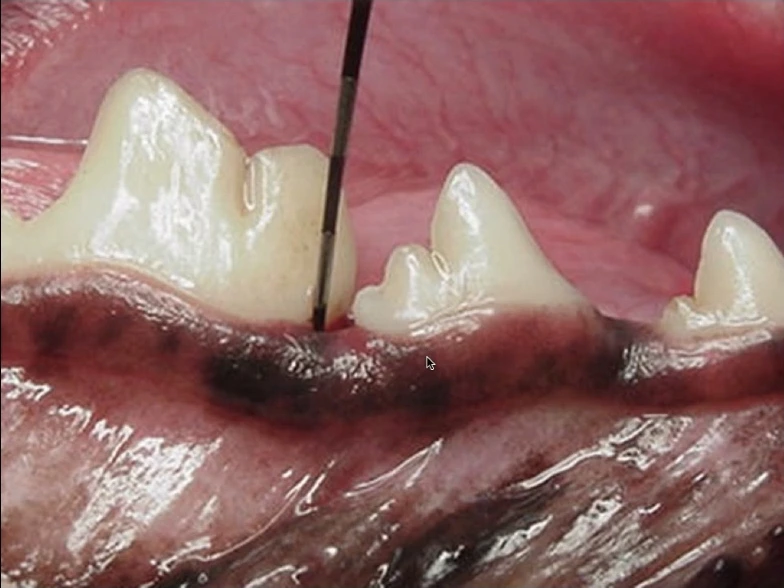

(These photos are of the same tooth)

These pictures are all the same tooth!

The first picture shows why “non-anesthetic dentals” can give people a false sense of security. This picture shows a periodontal pocket, but you don’t see the abscessed tooth root that is causing the pet significant pain. The picture looks benign when there is actually significant pathology.

Finally, the 3rd picture shows the actual tooth. The infected (painful) tissue has been cleaned away from the tooth. Remember how benign it appeared on the first picture. This tooth needs extraction. Without xrays the pet would have suffered silently in pain.